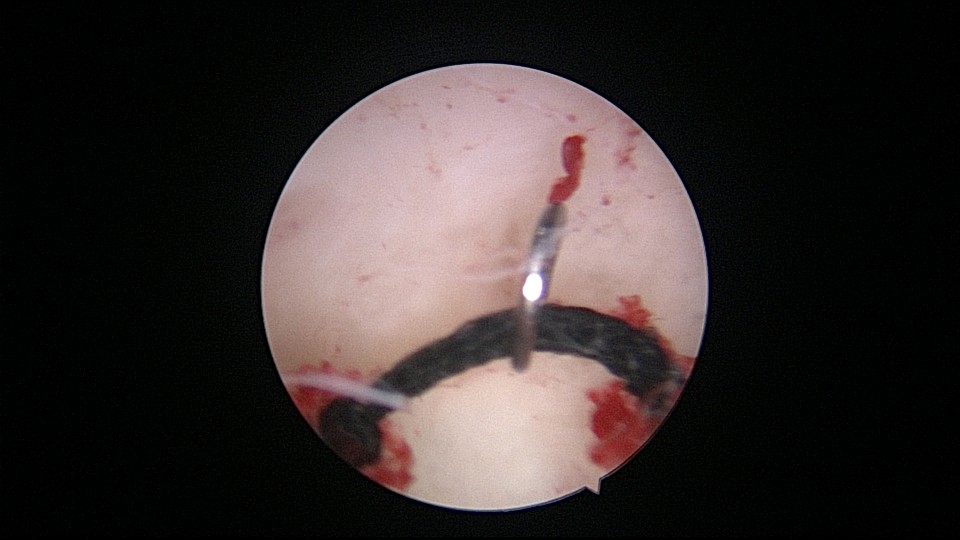

患者42岁,G6P2,剖宫产2次。2025年2月,停经48天,计划外妊娠,要求终止妊娠并放置节育环,考虑终止妊娠后宫腔大,担心环移位或脱落,要求固定节育环。γ环没有尾丝,用4号丝线连接环及不锈钢挂钩,将挂钩插入宫底肌层固定节育环。异物钳夹持挂钩送入宫腔可能在宫颈管皱襞上受阻,可以用中弯钳将挂钩送入宫腔下段,然后异物钳夹持挂钩插入宫底肌层。2025年3月复查B超,节育环位置正常,环顶端距宫底1.8cm。